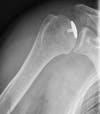

Photos: Arthroscopic pioneer, Dr. Steven Chudik, recently received a patent for a minimally invasive, total shoulder replacement method. The current procedure used by orthopaedic surgeons is open surgery and requires the dislocation of the patient’s shoulder and cutting of the rotator cuff muscles. Dr. Chudik’s new procedure is minimally invasive and avoids dislocation and muscle cutting and most important, preserves bone so the patient has options in the future should further surgery be necessary. Shown above are some of Dr. Chudik’s minimally invasive surgical instrument innovations and an X-ray of a partial resurfaced humeral head with one of his surgical advancements implanted. Dr. Chudik is a partner at Hinsdale Orthopaedics and founder of the Orthopaedic Surgery and sports Medicine Teaching and Research Foundation (OTRF), a nonprofit foundation dedicated to research and education as a means to help prevent injuries and keep people active.